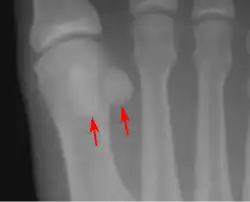

Sezamská (též sesamská, lat. os sesamoideum) kost je taková kost, která je uložená (vmezeřená) ve šlaše svalu. Svým tvarem připomíná sezamové semínko, odkud pochází jejich název. Podobných kostí je v lidském těle více, největší z nich je čéška umístěná v přední části kolenního kloubu. Dvojice sezamských kostí se rovněž vyskytuje v metakarpofalangovém a metatarsofalangovém kloubu. Jejich další výskyt a velikost se může u různých jedinců lišit. Za kost původem sezamskou se považuje i hrášková kost.